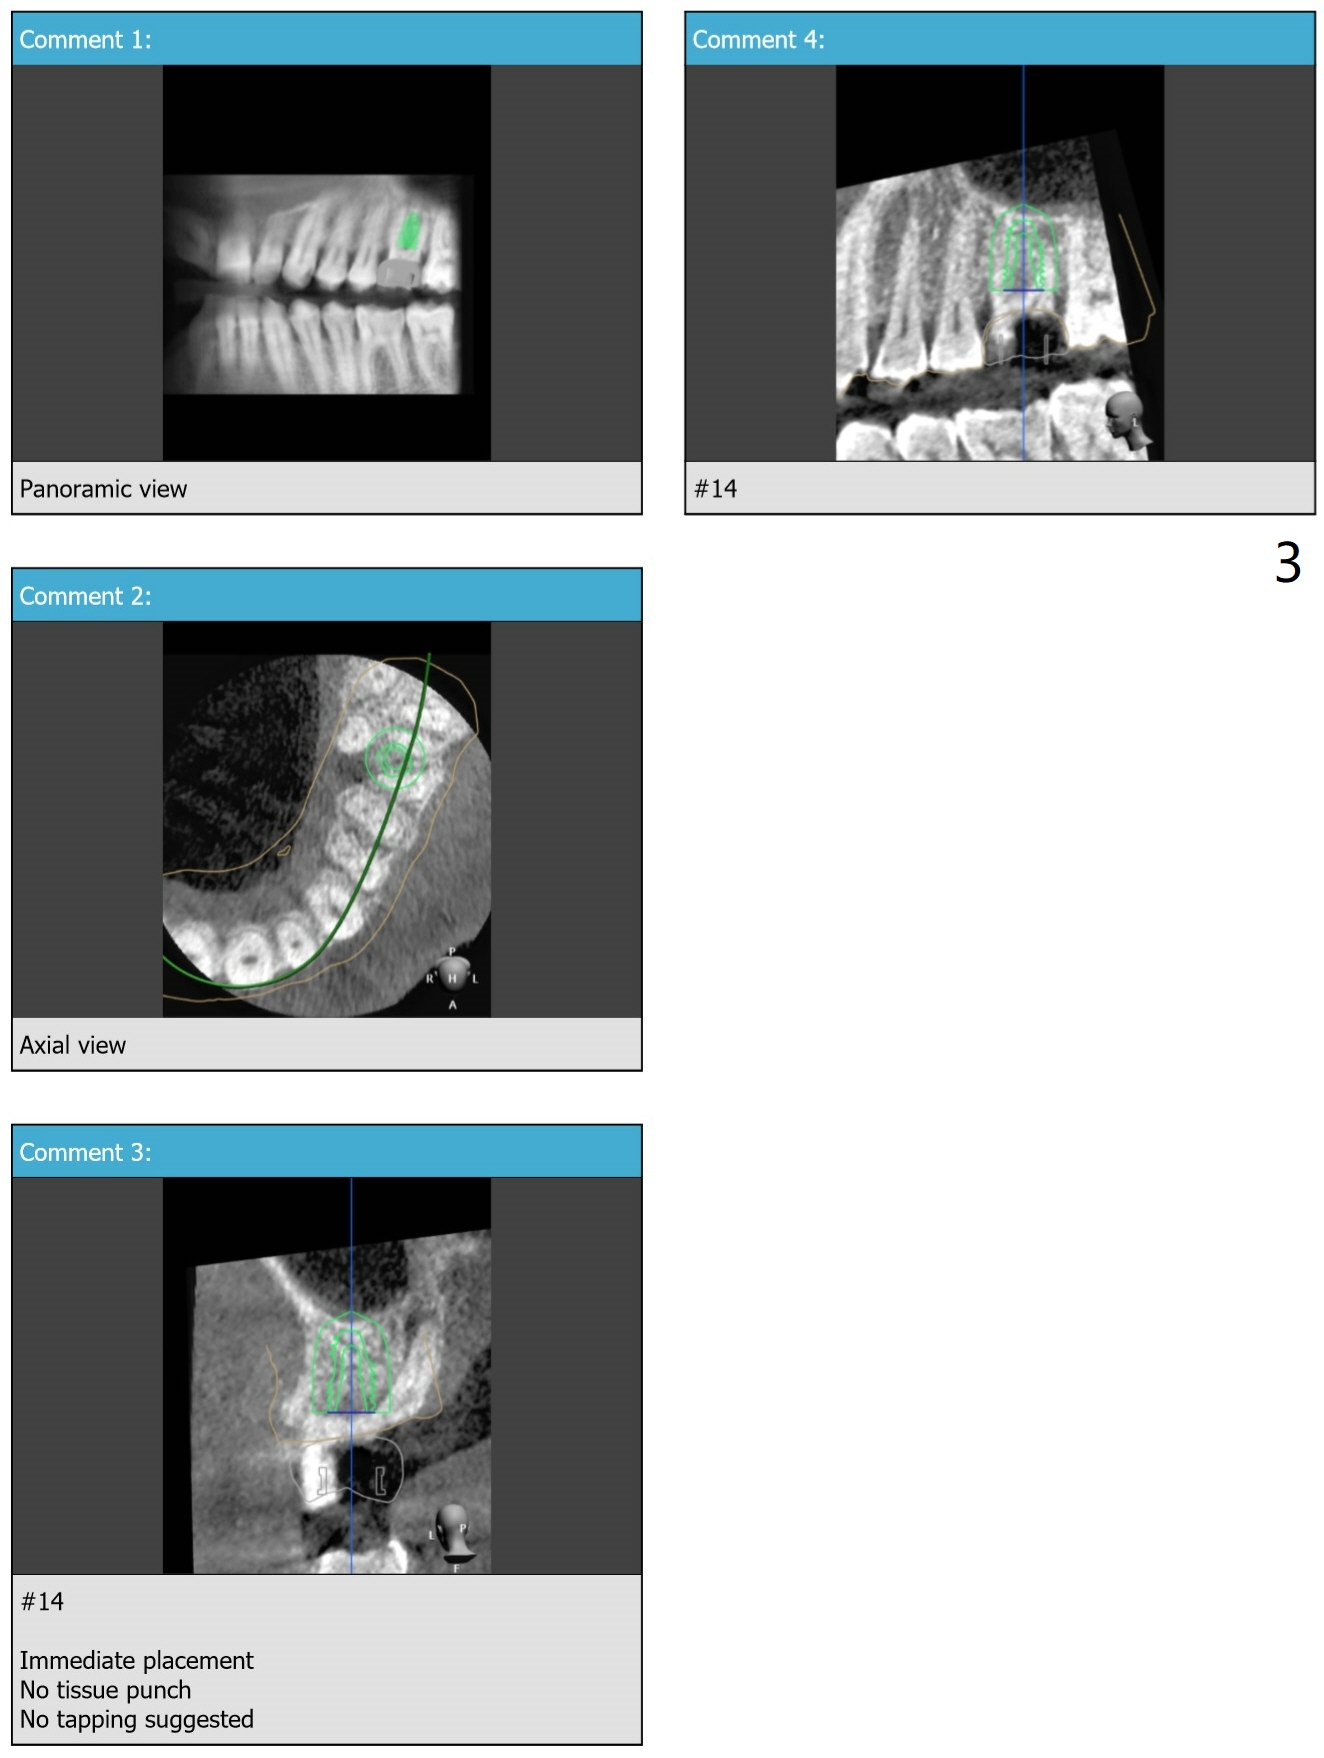

Short Implant with Palatal Shield

Try to place a 5x9 mm implant. After use of the last 2nd drill (and probe), use the narrowest drill to the depth and probe.